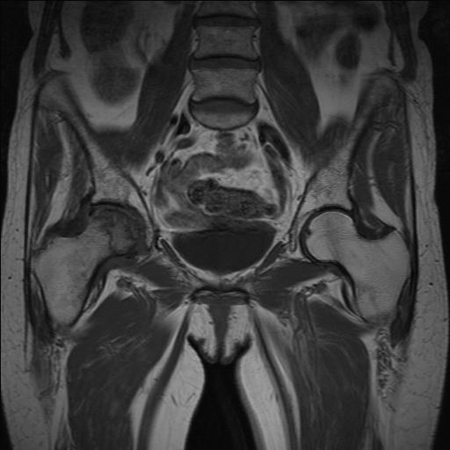

MRI of the hip

Test

Study of choice for diagnosing or excluding stress fractures, osteomyelitis, or early-stage osteonecrosis. The reported sensitivity of this modality varies widely (47% to 91%).[18][19]

Clinical correlation is vital.

Labral pathology may be incidental finding.[Figure caption and citation for the preceding image starts]: MRI demonstrating inferior right femoral neck stress fracture (compression-sided)From the collection of Cedric J. Ortiguera, MD [Citation ends].

[Figure caption and citation for the preceding image starts]: Osteonecrosis of the right femoral head seen on MRIFrom the collection of Cedric J. Ortiguera, MD [Citation ends].

Result

soft-tissue injuries, bone abnormalities including malignancy, and stress fracture